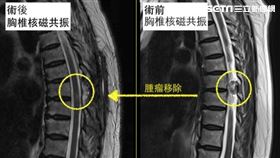

下肢麻木=腰椎退化?小心脊椎腫瘤

陳小姐50歲,最近半年來感覺下肢麻木,曾經接受過復健...